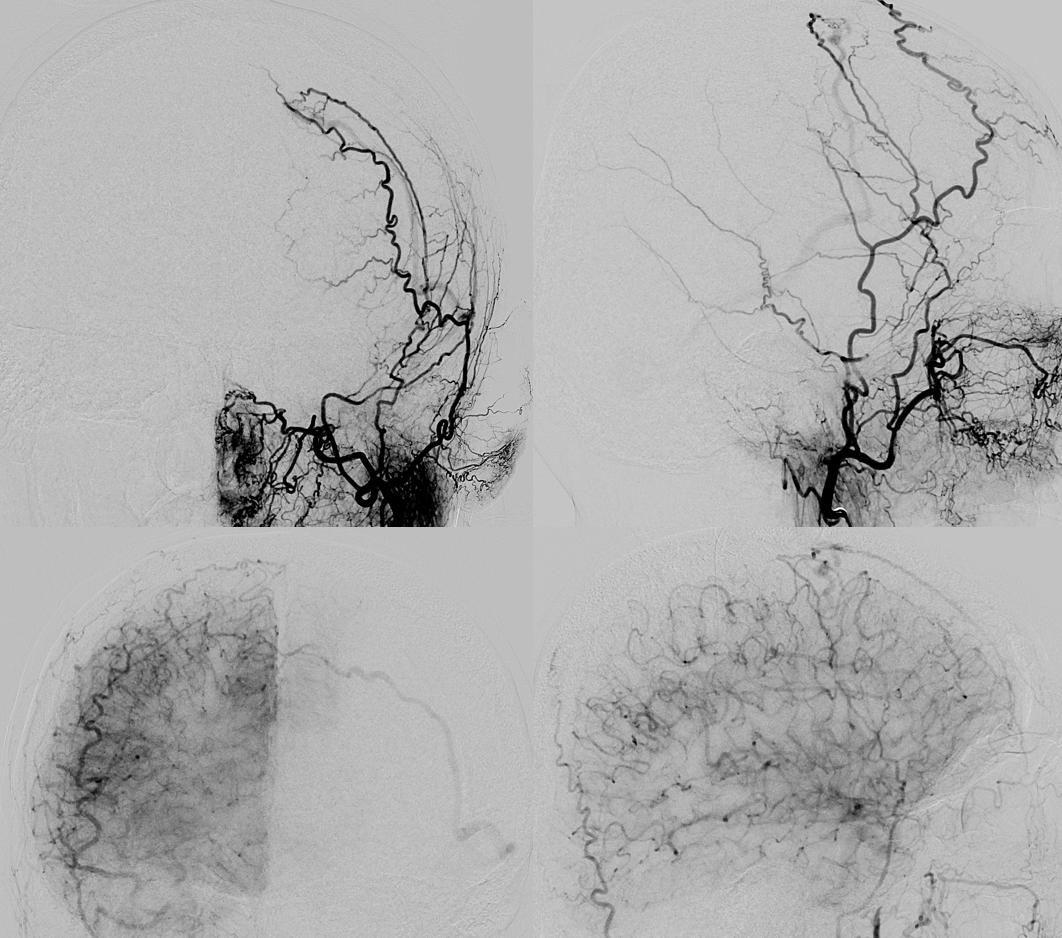

Right ECA — also unusual appearance of the MMA

Here is the detail. There is a short segment proximal MMA occlusion, with reconstitution from the anterior deep temporal